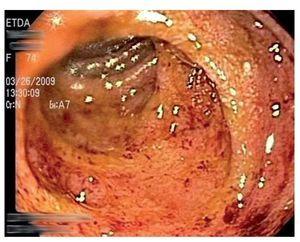

Mujer de 74 años de edad, residente del Distrito Federal, con antecedente de esclerodermia y cirrosis biliar primaria en tratamiento con ácido ursodeoxicólico. Inició ocho días previos a su ingreso con dolor abdominal epigástrico, náusea, distensión abdominal y melena. A la exploración física se encontró con signos vitales normales, mucosas pálidas, peristaltismo disminuido, sin otros hallazgos relevantes. Los exámenes de laboratorio mostraron hemoglobina 10.6 gr/dL, hematocrito 31%, leucocitos totales 8700 células/dL (4% de eosinófilos). Se le realizó endoscopia de tubo digestivo, que evidenció esofagitis erosiva grave, gastropatía eritematosa petequial, múltiples úlceras gástricas de 10 mm de diámetro con base de fibrina (Figura 1) y duodenitis erosiva (Figura 2). Se tomaron biopsias de los bordes de las ulceras y se envió en formol a estudio histopatológico que informó estrongiloidiasis gástrica, con inflamación crónica y aguda sin Helicobacter pylori (Figuras 3 y 4).

¿ Figura 3. Hematoxilina-eosina: Estrongiloidiasis gástrica.